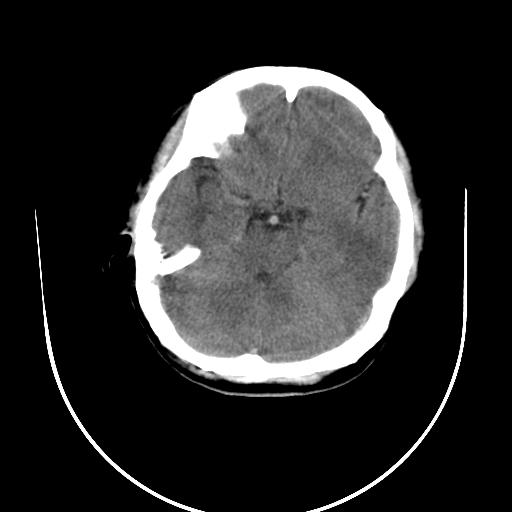

标题: CT10010:女/24岁,癫痫一周,发作时间不固定. [打印本页]

标题: CT10010:女/24岁,癫痫一周,发作时间不固定.

右侧额叶正常吗?

右额叶镰旁饱满.

右侧外侧沟?中央沟?可能有问题,不知以前有没有癫痫过,最好是增强下,排除局部血管畸形等病变

倒数第6幅图中线结构有点偏,而侧脑室额角未见异常,可结合增强扫描。